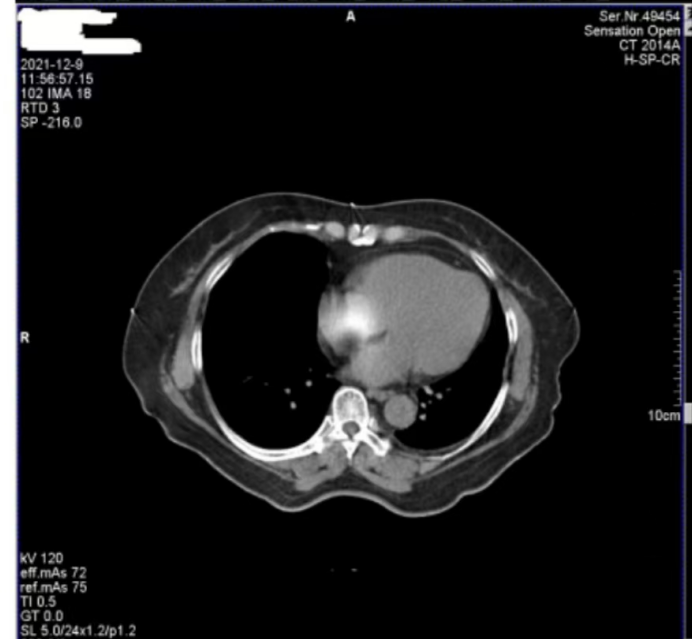

医院反映,西门子Definition型CT机在进行患者扫描时,图像上会偶发两种伪影。一种是斜线状伪影(图 1),另一种是中心不规则高密度伪影(图 2)。其中,斜线状伪影对诊断影响较大,时常导致医生无法准确判断患者病灶情况,医院希望我们尽快排查并解决问题。

图2

接着,我们将目光转向图 2 中的中心不规则高密度伪影。为了找出伪影成因,我们对设备的多个关键部件进行了检查。首先查看了玻璃条、探测器表面以及准直器表面,确认这些部位是否沾有造影剂,因为造影剂残留有时会导致伪影产生,但检查结果显示这些部位均干净无污。

随后,我们检查了特氟龙滤线器部件。特氟龙部件采用金属材质,具有较高的稳定性,通常不会出现断裂等情况,因此可以排除因特氟龙部件异常导致伪影的可能。考虑到这种中心伪影是偶发出现的,我们开始推测其他可能性。结合球管的结构和工作原理,我们怀疑是球管内部存在杂物。球管内部有油路循环系统,若有杂物混入其中,在曝光过程中,当杂物恰好处于出射线的位置时,就会对射线产生干扰,从而在图像中心形成不规则的高密度伪影。